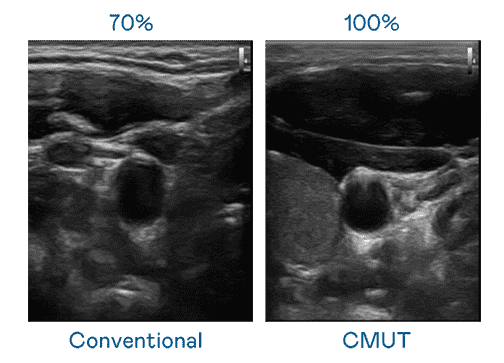

CMUT 技术是一种用电容式微机电元件来产生超音波讯号的技术。。。与传统 PZT 压电式技术相比,,,CMUT 频宽增加 30%,,,,更宽频的超音波讯号让影像解析度大幅提升,,,是实现高影像品质医疗超音波扫描、、、促进精准医疗发展的关键技术。。。。

大频宽带来超清晰影像

超音波影像的解析度高低,,,首先取决于探头能发出的讯号频宽。。。。壹号平台 CMUT 可提供高清晰的超音波讯号,,,,提供高频宽、、、、高灵敏度、、、、影像纹理细节更高的超音波影像,,,,协助医护人员缩短影像判读时间及利用精准的医疗影像进行诊断。。